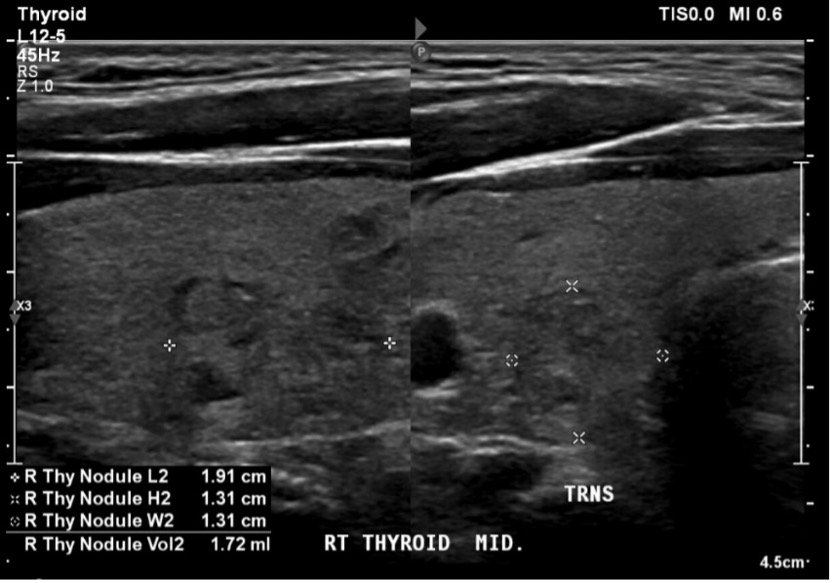

Due to thyroid cancer being a complication of longer-term minocycline treatment, an otolaryngologist evaluated the patient next. After performing a thyroid sonogram, this evaluation revealed multinodular goiter with two concerning nodules. The provider recommended observation and a repeat thyroid sonogram in six months.